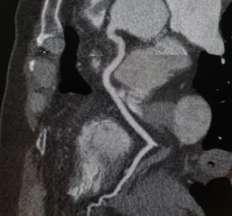

Lapresenciadecalcificacionesenlas arteriascoronariasesindicativode enfermedadaterosclerosa,yrepre‐sentademaneragruesalacargadeenferme‐dadenestas.

Elpuntajedecalciohademostradoserunex‐celentepredictordeeventosadversos cardiovascularesindependientementede otrosfactoresderiesgo.Lamediciónde calciocoronariotieneimportanciadiagnós‐ticatantocomoterapéutica.

Desde1990a2000sehanrealizadomúltiples estudiosalargoplazoendiversospaíses,que hanevidenciadounaintensaasociaciónentre elcalciocoronarioyloseventoscardiovascu‐laresmayoresenpersonasasintomáticas.

Elmétododeelecciónparalacuantificación delcalciocoronarioesmedianteelpuntajede Agatston,elcualserealizaconunestudiode tomografíasimple,sincronizadaconelectro‐cardiogramaelcualpermitecategorizaralos pacientesengrupossegúnsuriesgo.

Sinembargoporsísolonopuedeestimarel gradodeestenosisdelasplacas,paralocual serequiereunestudiocontrastadoelcual permiteunaadecuadavisualizacióndelases‐tenosisconadecuadaprecisión.Losestudios deangiotomografíapermitenladetección oportuna,lacaracterizacióndelesiones, evaluarlaextensióndelaenfermedadydar seguimientoalaslesionesquepudieranser significativas,pudiendoefectuarrecomen‐dacionesparauntratamientooportuno.

Esrecomendablerealizarseenpacientescon condicionestalescomodiabetes,hiperten‐sión,edadavanzada,hipercolesterolemia, síndromemetabólico,antecedentesfamiliares deenfermedadarterialcoronaria,entreotras. EnCDIcontamosconlatecnologíaparallevar acaboestosmétodosdeestudio,deforma individualizadaparacadapaciente,conel objetivodeproporcionarestudiosdelamayor calidad,quesetraduzcanentratamientos oportunosyunamejorcalidaddevida.